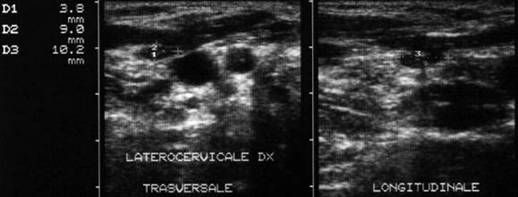

Loja laterocervicala dreapta.

Loja laterocervicala stanga

Femeie 31 ani. Leziuni hipoecogene, neomogene laterocervical bilateral. Tiroidectomie totala pentru neoplasm papilar cu extensie extracapsulara si metastaze linfonodale (T4 N1 M0) in urma cu 2 ani. Terapia radiometabolica.

Examen citologic: celule epiteliale gigante ca in granulomul

de corp strain; fibroza cronica granulomatoasa supurativa. Tireoglobulina din lichidul

de lavaj: nedozabil.

Aceeasi pacienta – fara semnal de vascularizatie

interna.